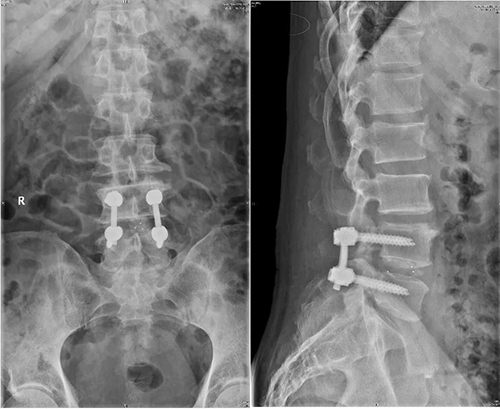

患者术后复查的X线片

患者摆好手术体位后,崔新刚教授精准定位责任间隙,在脊柱内镜辅助下,各解剖结构得到清晰呈现,崔新刚教授精准完成双侧神经减压、椎间融合和椎弓根螺钉固定,整个手术过程历时不到2个小时。手术顺利完成,老林自觉腰部及其下肢疼痛明显缓解。经过积极术后康复与治疗,老林术后5天就顺利出院。